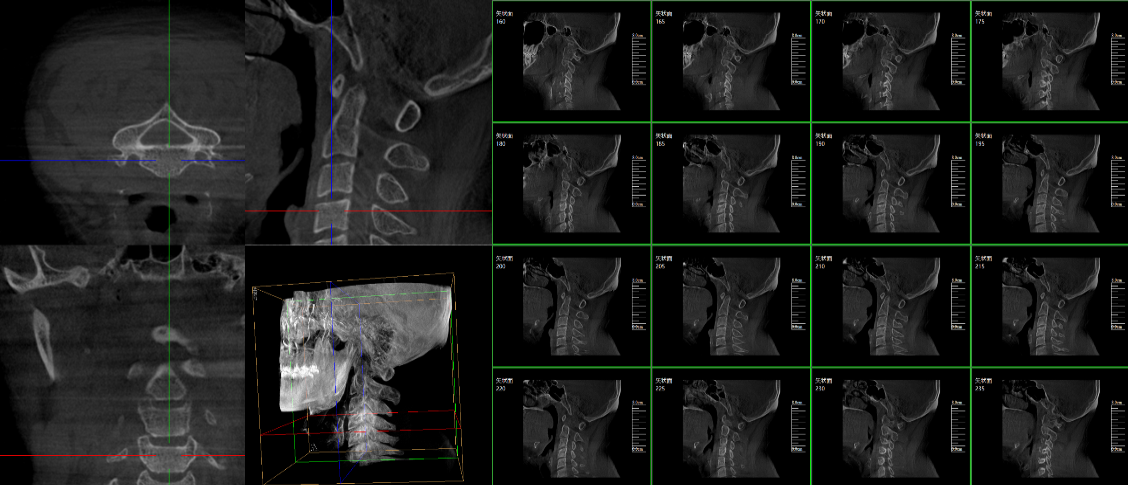

現(xiàn)在很多廠家或者經(jīng)銷商都在推廣三維c型臂,那么,三維c型臂是什么意思?三維c型臂是一款新型C形臂,實(shí)現(xiàn)了術(shù)中影像從二維到三維的飛躍。通過不同方位的斷層圖像,能夠更清晰、完整地顯示椎體及其附件的解剖學(xué)結(jié)果,直觀地分析病變與周圍組織的立體空間關(guān)系,三維斷層成像能夠使手術(shù)模擬和手術(shù)方案的制定更加準(zhǔn)確。

普愛醫(yī)療是專業(yè)生產(chǎn)c型臂廠家,在國內(nèi)率先掌握三維成像技術(shù),繼國內(nèi)首例三維影增c型臂后,又推出國產(chǎn)品牌等中心平板移動(dòng)式三維C形臂X射線機(jī)——天弓PLX7500三維c型臂。該設(shè)備擁有優(yōu)異的術(shù)中三維成像技術(shù);高品質(zhì)數(shù)字化影像鏈;超大三維成像區(qū)域;穩(wěn)定全面的圖像采集;便捷簡易的操作體驗(yàn);全電動(dòng)的運(yùn)動(dòng)控制;低劑量模式;無線導(dǎo)航傳輸;多屏同顯等特點(diǎn)。

脊柱外科的應(yīng)用:有研究表明,在三維c型臂圖像引導(dǎo)的下頸椎或胸椎后路螺釘置入術(shù)中,螺釘正確置入率可達(dá)92.7%,在三維c型臂圖像引導(dǎo)的椎間孔腰椎椎間盤融合術(shù)中,術(shù)者被輻射總量明顯降低。此外三維c型臂可以搭配骨科手術(shù)導(dǎo)航和機(jī)器人使用,能將該過程智能化和準(zhǔn)確化,進(jìn)一步提高螺釘?shù)闹踩肼省?/span>

創(chuàng)傷外科的應(yīng)用:由于創(chuàng)傷外科的患者多數(shù)為急、重癥患者,以致術(shù)前準(zhǔn)備時(shí)間較短,很多都需行急診手術(shù),三維c型臂可以在術(shù)中實(shí)時(shí)重建三維圖像,使手術(shù)醫(yī)生對(duì)一些復(fù)雜骨折更加充分的了解,并且能夠在術(shù)中即時(shí)校正螺釘?shù)奈恢茫泳_地置入固定器材,減少術(shù)中及術(shù)后發(fā)生并發(fā)癥的幾率,極大限度地縮短螺釘置入時(shí)間。